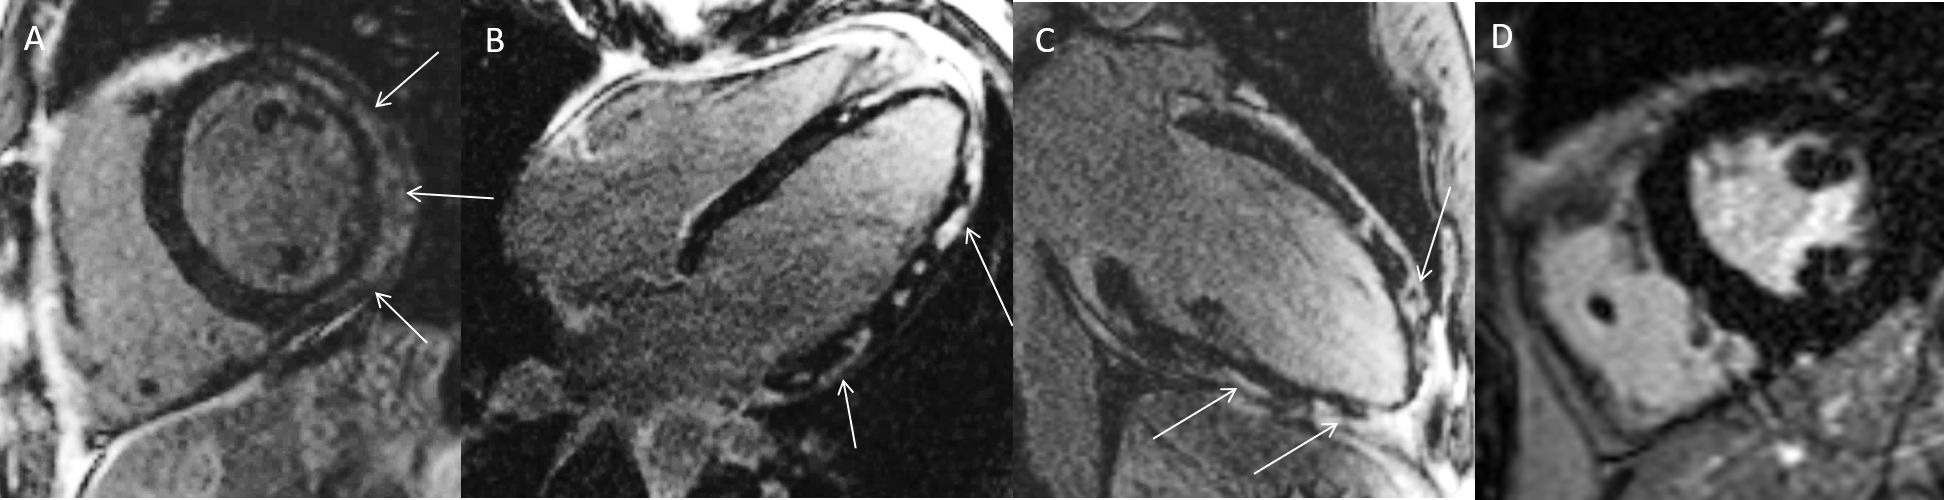

Patient mit Schmerzen in der Brust, ST-Hebungen im EKG sowie deutlich erhöhten Herzenzymen. In der Herzkatheteruntersuchung keine Engstellen. Im CMR Nachweis von mehreren hellen Arealen (Pfeile) in den Spätaufnahmen nach Kontrastmittelgabe (=Late Enhancement) passend zu einer Herzmuskelentzündung = Myokarditis (A-C).D = Gesunder Vergleichspatient (gesunder Herzmuskel stellt sich in den Spätaufnahmen dunkel dar).